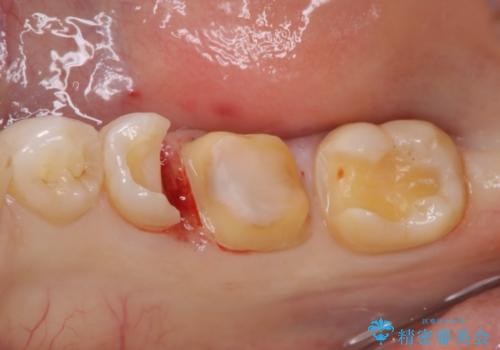

- 歯と歯の間によくものが詰まるということで来院された患者様です。

銀歯のある部分によくものが詰まるようで、診断の結果セラミックにて治療を行う計画を立てて

銀歯を外し他の歯も虫歯があったためそちらも一緒に治療を行いました。